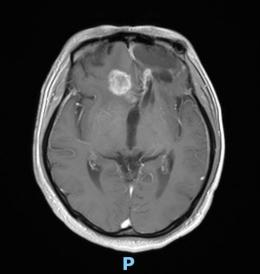

44歲的郭先生(化姓)為膠質(zhì)瘤復(fù)發(fā)患者,復(fù)查發(fā)現(xiàn)顱內(nèi)占位進(jìn)行性進(jìn)展1周,MRI檢查提示瘤體已累積到胼胝體,且瘤體位置較深,手術(shù)難度極高。面對這一挑戰(zhàn),王虎教授團(tuán)隊(duì)決定采用多種先進(jìn)技術(shù)輔助手術(shù),其中最為引人注目的就是首次引入的細(xì)胞級顯微鏡EndoSCell?。該設(shè)備是目前全球唯一實(shí)時(shí)在體細(xì)胞級顯影的儀器,可以輔助醫(yī)生從細(xì)胞層面區(qū)分腫瘤組織與正常組織,從而做到細(xì)胞級精準(zhǔn)切除。

患者術(shù)前核磁影像

整個(gè)手術(shù)過程在“腦醫(yī)匯”平臺進(jìn)行了全程直播,吸引了近千位神經(jīng)外科領(lǐng)域的專家學(xué)者觀看,他們紛紛對王虎教授團(tuán)隊(duì)的精湛技藝和EndoSCell?的先進(jìn)技術(shù)表示贊賞。術(shù)后,患者的生命體征平穩(wěn),CT及MRI檢查顯示腫瘤切除滿意,無明顯出血和并發(fā)癥。患者神志清醒,精神狀態(tài)良好,目前恢復(fù)良好。